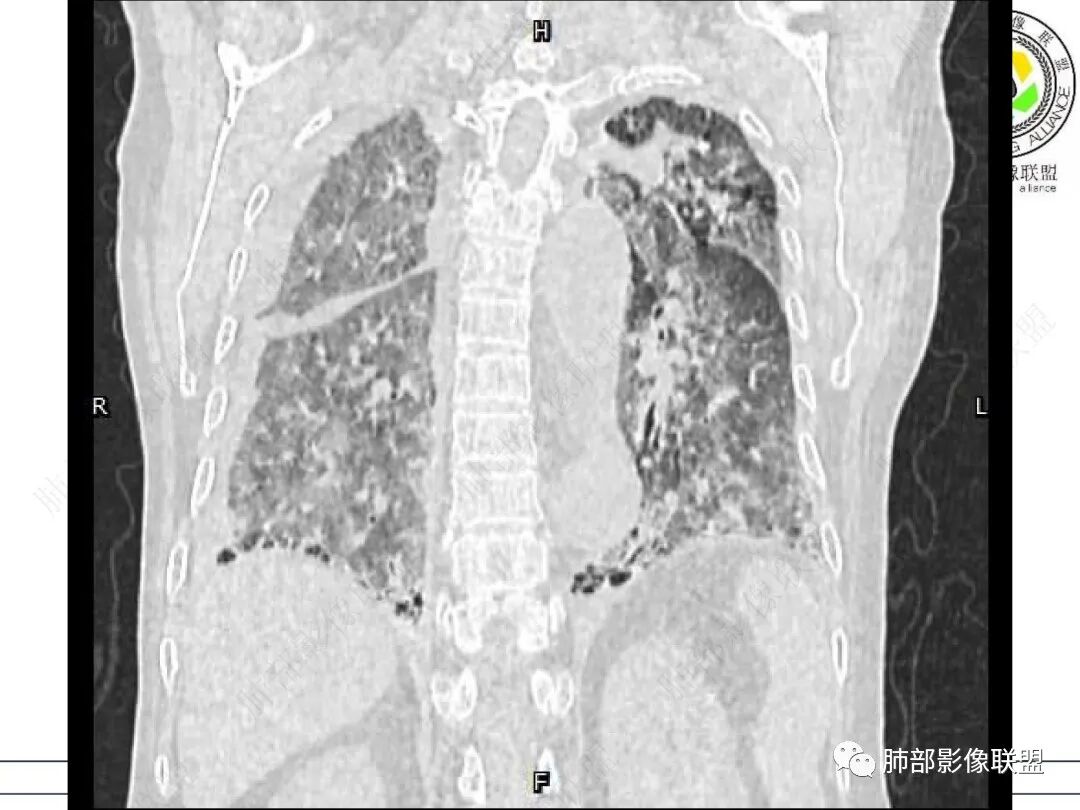

老年,外阴溃疡加发热,感染指标明显有异常,血气分析,过度呼吸及低氧血症,宿主因素,糖尿病和激素,基础疾病RA。影像,双下肺体积有缩小,有蜂窝?双肺磨玻璃,多发结节,双侧胸水。树芽不明确。是否有旧片,这个患者有UIP背景,是否感染或者UIP急性加重,或者基础上合并肺栓塞及肺水肿?长期激素,没有提供CD4细胞亚群,存在2种情况,1,风湿病没有压制住,肺考虑CTD相关性间质改变,压制过猛,结合感染指标,奴卡是有可能的。激素加糖尿病,结核也带排,激素加磨玻璃加G实验阳性,PCP也带排,临床信息太少,进一步排查

一元论解释不了整个的病程:从临床的角度分析,第一,该患者是离异女性,这种的去收,我倒是建议入院之后就要把,艾滋这一套查了,第二,该患者有类风湿性关节炎的病史,长期服用免疫制剂,而且有糖尿病的病史,这两种疾病叠加在一起,肯定会导致他的免疫力低下的,第三个,他的血常规中的白细胞不高,c反应蛋白相对来说比较高,这个可以看成是类风湿性关节炎活动的指标,但是这个人的PCT高,类风湿性关节炎活动导致PCT高的不多,这个人的G特别高,而且这个人的肾小球滤过率已经降低了,正常的肾小球滤过率是80到120,这个人是68,而且这个人的血气分析是一个明显的一型呼衰的表现,二氧化碳分压特别低所以明显存在着过度通气的情况结合临床所说的发热一周,这个人应该不是一个单纯的疾病,可以解释的。那么,从影像的表现看,双下肺的那些蜂窝样的表现符合UIp的表现,这个可以看成是类风湿性关节炎导致的继发性的间质改变,这就是双肺弥漫的渗出性的影子,结合患者G阳性(这些影子看上去不像曲霉菌的感染,也不像白念的感染)所以说还是高度怀疑pcp的,你仔细看一下它的矢状位,叶间裂好像还有渗出,还有积液,加上患者双侧胸腔积液,那么我觉得肺水肿的因素还是有的,这就是PCT五点多,是否还合并着其他的细菌感染?综上所述,我觉得这个人可能存在以下问题,第一个类风湿性关节炎导致的UIP,第二个免疫力低下导致的pcp,第三个肾小球滤过率下降导致的肾源性肺水肿?或者是心源性肺水肿,这就是可能还合并了其他的细菌感染。患者离异,不知道什么时候离异的,目前,71岁了,如果离异的时候比较年轻的话,是否是存在多个性伴侣?所以说,艾滋病这一块也不能排除

老年女性,外阴溃疡伴发热,有类风、糖尿病病史,血象及炎症指标高,G试验升高;影像:磨玻璃密度(中央分布为主)胸膜下蜂窝状改变心影增大、两侧胸腔少量积液;小叶间隔增厚,结节;考虑:1.中央分布为主的GGO需考虑:肺水肿、出血、PJP、肺泡蛋白沉着症;2.胸膜下间质性改变蜂窝肺,需考虑UIP、CTD-ILD,综合:两元论:CTD-ILD奴卡,或肺水肿

①影像表现复杂:较弥漫间质性改变,对称磨玻璃密度为主,小叶间隔增厚,有一定重力分布趋势,未见明显纤维化,气囊及蜂窝位于肺边缘,未见典型“月弓征”。心脏影增大,双侧胸腔积液。

这即可见于间质性肺病,也可见于真菌感染(如PJP)、病毒感染,类风湿,以及肺水肿等等。

一般而言,如存在磨玻璃密度影浑浊,有重力分布趋势,肺表面蜂窝影,胸腔积液等等,并不常见于单纯PJP,除非其他因素叠加。

患者存在肺水肿应当是合理的解释。其他旁证还有,心脏影增大,肾小球滤过率降低,双侧胸腔积液等等……

但这些改变却足以影响我们对PJP的影像学特征的观察。

上肺斑片影、结节影,夹杂纤维条索影,边界清楚,新旧不等,胸膜牵拉明显等等,符合较典型继发性肺结核表现,但它却未必是此次就医主要责任病原体!

实验室白细胞不高,C反应蛋白、PCT增高,淋巴细胞显著低(CD4项阙如),G试验值相当高。肾小球滤过率降低,呼衰等等。

应当说本并例实验室检查是有理由高度怀疑存在肺孢子菌肺炎的。